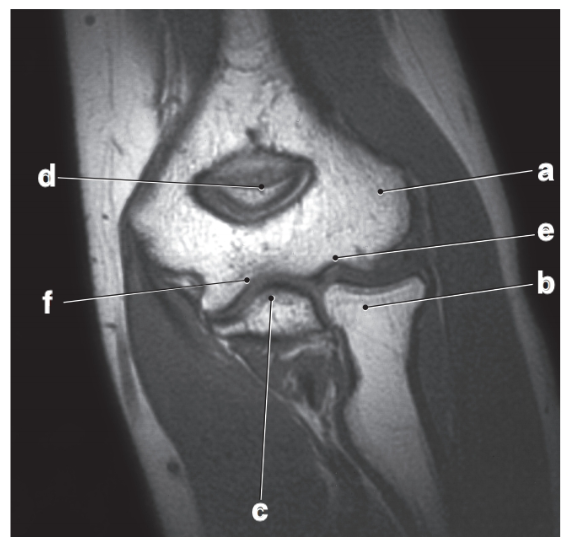

Which letter is the popliteal artery?

A

What is letter b?

Medial meniscus

What is letter d?

posterior cruciate ligament

Which letter is pointing to the posterior cruciate ligament?

e

Triangular fibrocartilage complex

Which letter is pointing to the patellar ligament?

b

medial collateral ligament

Which letter is pointing to the anterior cruciate ligament?

c